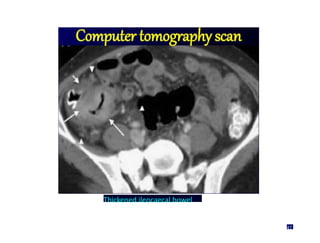

Computertomographyscan

Thickened ileocaecal bowel